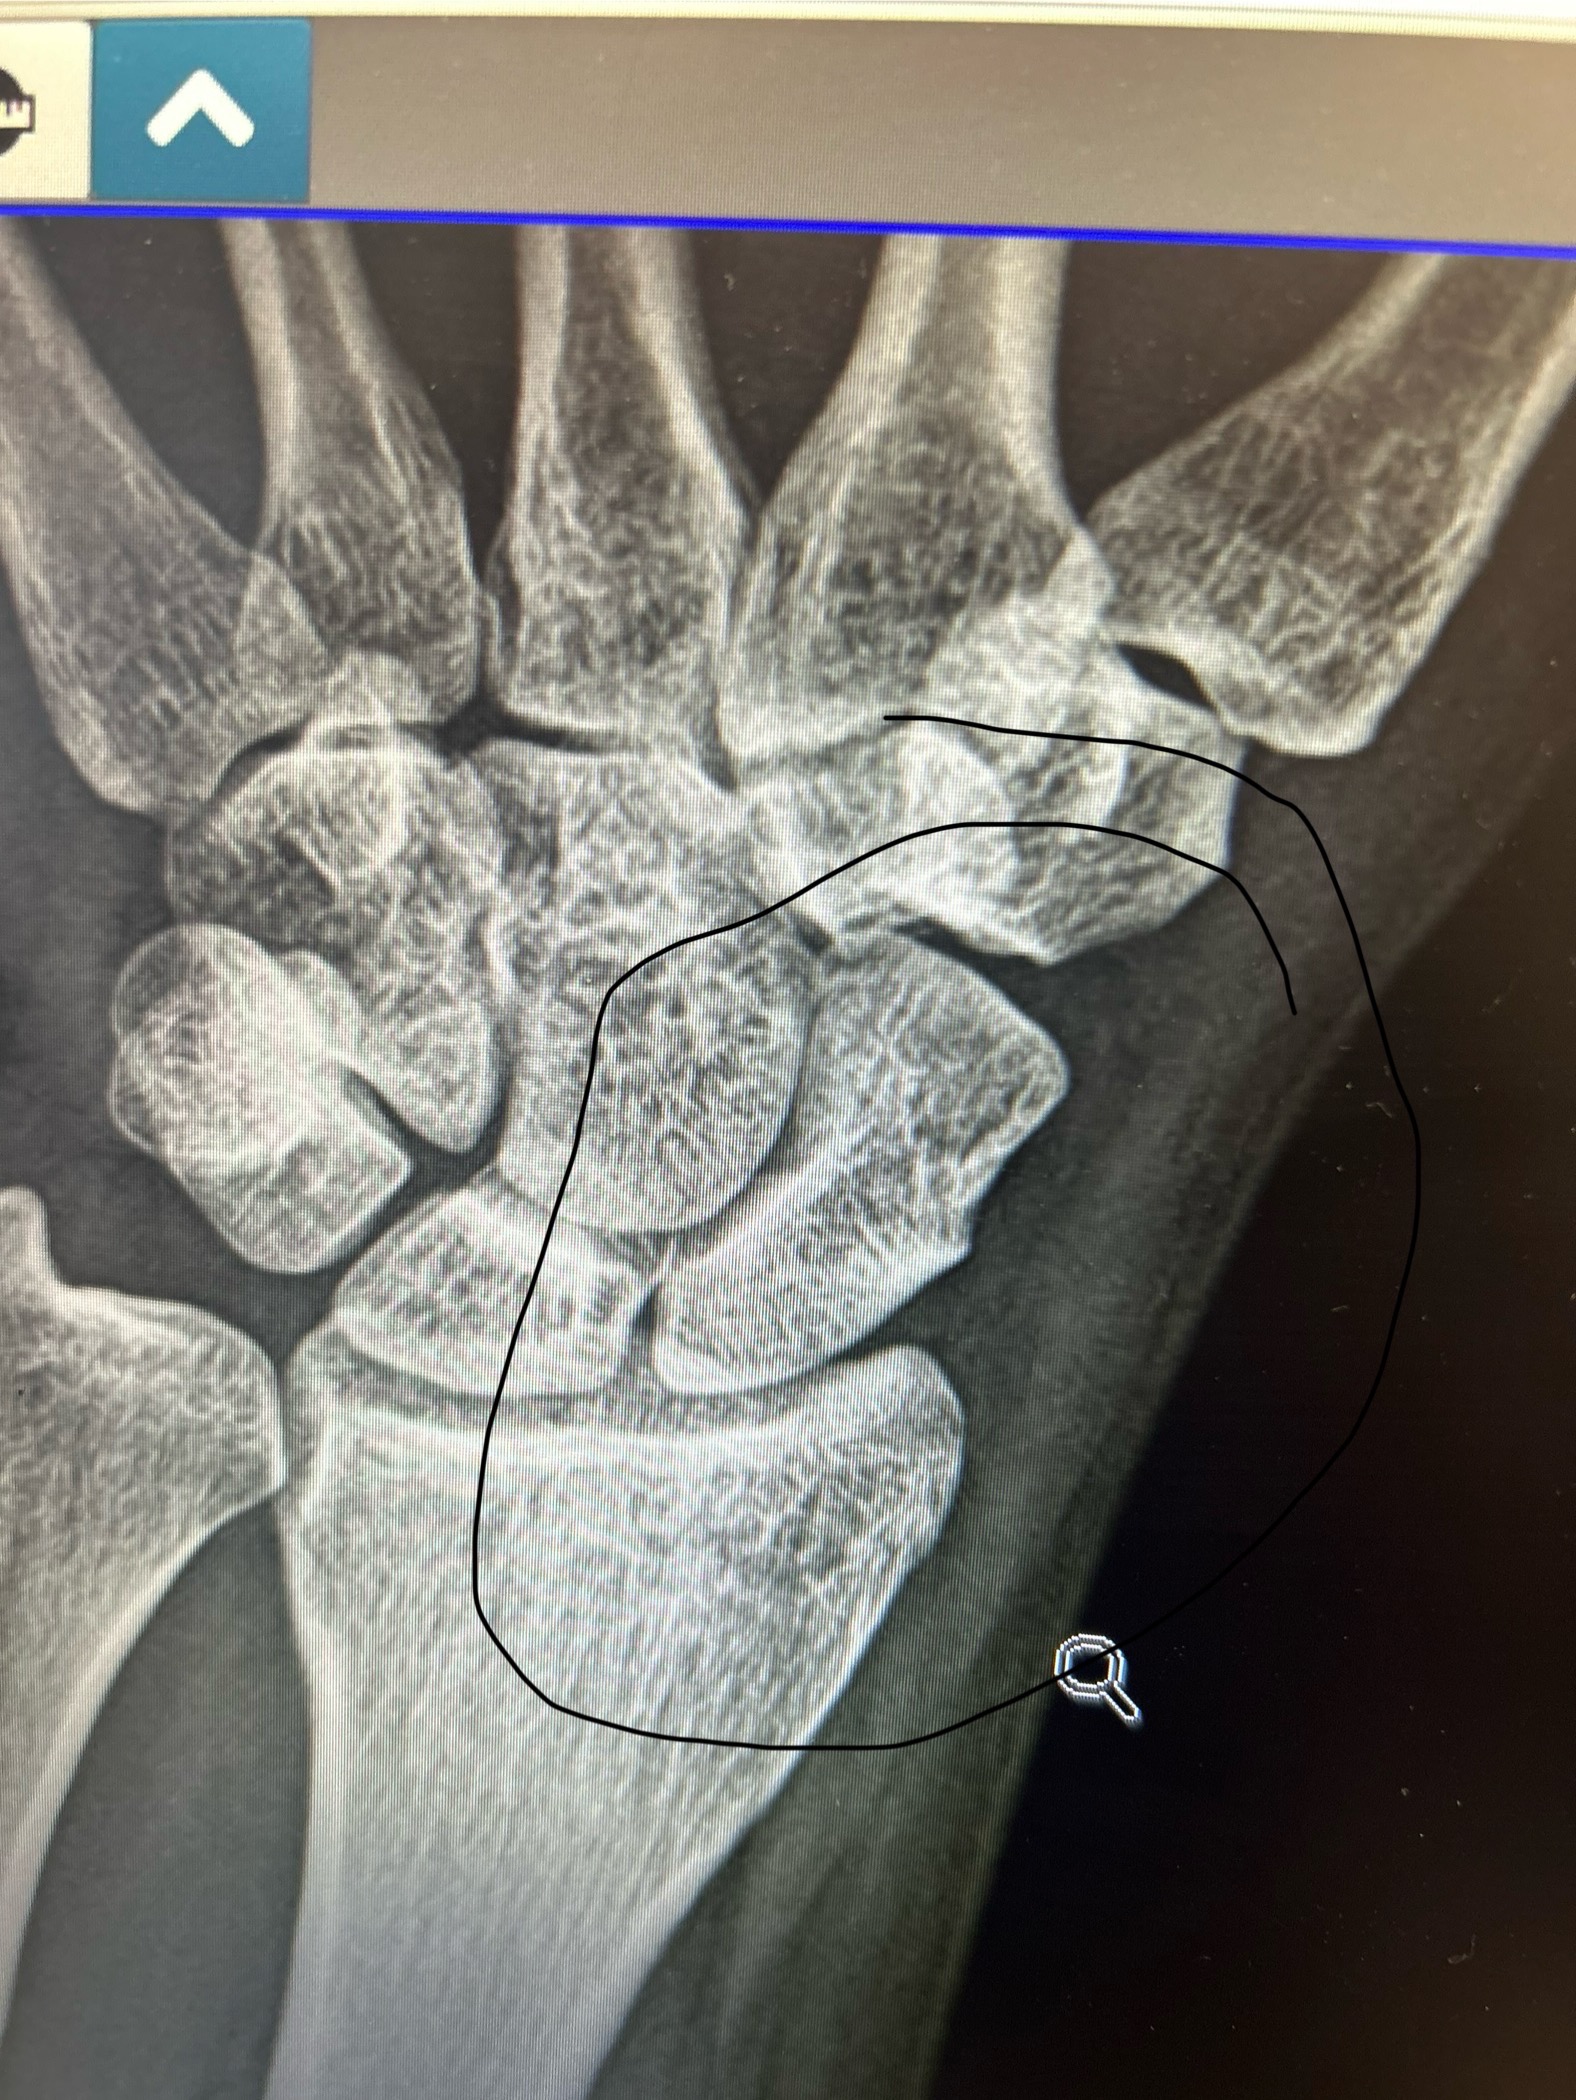

On 6/9, I slipped and fell and broke my wrist. We thought it was just a sprain, but after visiting an ortho specialist, we found out I have a break in my hand/wrist which seems to be healing itself, thank God. Bad news, I'm out of work for another 5 weeks. Bills are piling up, and I have no one. Workman's comp is 60 percent of my income, which I can barely survive on.

If there would be any way you could find some generosity in your heart to help, I truly thought I would be able to go back to work tomorrow and now may need surgery depending on how this heals. WE ARE STRUGGLING. Neighbors have been kind enough to bring us veggies, but this would be a small buffer to help get through the next weeks. Even if you could contribute a dollar. Thank you so much.